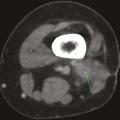

Striatopathie diabétique

COMPLICATIONS DU DIABETE

HYPERGLYCEMIE